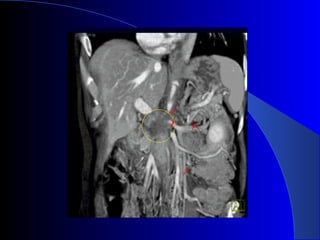

Estudios de imagen USG abdominal TAC helicoidal dinámica en tres fases: estándar de oro para diagnóstico y valorar resecabilidad CPRE RMN TEP Neoplasias páncreas. Rosesch Dietlen pag 545-560

Diagnóstico CLÍNICO: Avanzadoe incurable. LABORATORIO: Anemia, desnutrición, obstrucción biliar, hiperamilasemia. US: Sensibilidad: 80%, especificidad: 75%. (>3 cm). Ganglios, dilatación VB. TAC: Estudio inicial de elección. CPRE: Obstrucción del Wirsung. Dr. Nogueira de Rojas

Estudios de imagenUSG abdominal TAC helicoidal dinámica en tres fases: estándar de oro para diagnóstico y valorar resecabilidad CPRE RMN TEP Neoplasias páncreas. Rosesch Dietlen pag 545-560